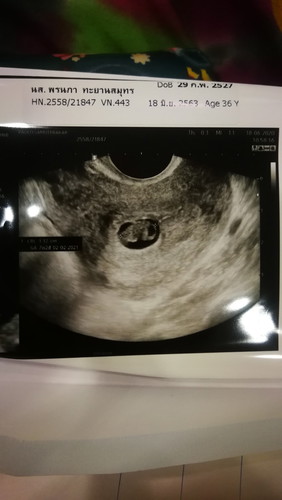

7week ตามหมอ 9 weekตาม แอฟ ไม่พบหัวใจเด็ก

อยากรู้ว่าปาฏิหาริย์จะมีไหม สัปดาห์หน้าหมอนัดเอาเด็กออก ตอนนี้เครียดมาก

สู้ๆนะคะ ขอให้ปาฏิหาริย์มีจริงนะแม่ น้องอาจจะยังเล็กเลยไม่เห็นหัวใจ สัปดาห์หน้าเห็นแน่แม่